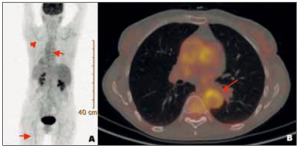

Artères temporales normales et syndrome inflammatoire

Mme B. consulte pour des arthromyalgies rhizoméliques, d’horaire plutôt mécanique, mais persistantes depuis un an. L’interrogatoire ciblé retrouve une hyperthermie vespérale à 39 °C depuis quelques jours, une perte de…